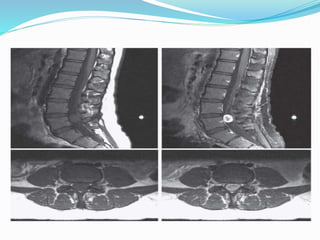

 MRI lumbosacral spine with contrast

Investigations  Specific : Xray lumbosacral spine (AP XTSX CC)  MRI lumbosacral spine with contrast  Relevant :  Routine :  CBC , SUCE ,PT/APTT/INR,Hep b & c , CXR